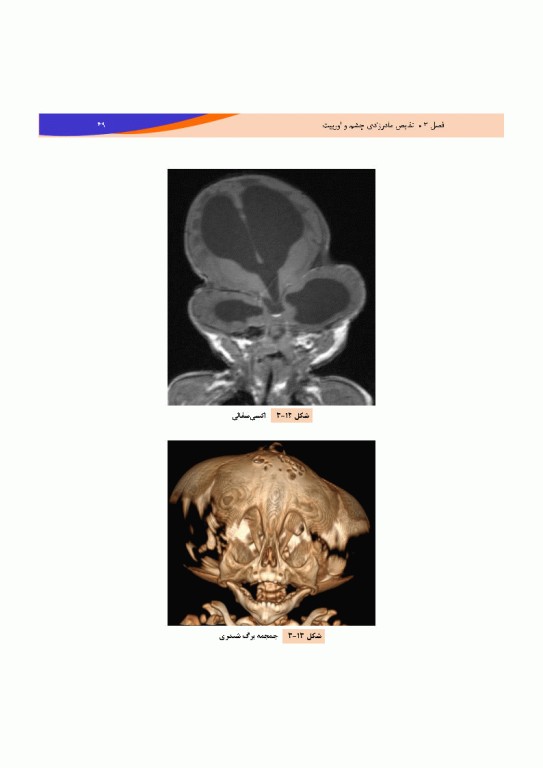

کتاب تصویربرداری پزشکی صورت و چشم نویسندگان رضا پرویزی، رضا احدی، مسیح ریخته­ گر، پوریا دانای سیوکی و مهسا نیک­چهر توسط انتشارات جامعه‌نگر به چاپ رسیده که مرجعی جامع تصویربرداری صورت و چشم است که با رویکردی دقیق و بالینی، آناتومی اوربیت، تکنیک‌های تصویربرداری و طیف وسیعی از ضایعات مادرزادی، تومورال، التهابی و تروماتیک را پوشش می‌دهد.

کتاب تصویربرداری پزشکی صورت و چشم ساختار مرحله‌به‌مرحله‌ا‌ی مباحث و همراهی آن‌ها با بیش از 360 تصویر ام آر آی و سی تی اسکن امکان یادگیری و تشخیص سریع‌تر را برای رادیولوژیست‌ها، چشم‌پزشکان، دستیاران و کارشناسان رادیولوژی فراهم کرده است.

·       بیش از 360 تصویر ام.آر.آی و سی­تی اسکن با توضیح آموزشی

·       پوشش کامل آناتومی، بیماری‌ها و تومورهای صورت، اوربیت و ساختارهای مجاور